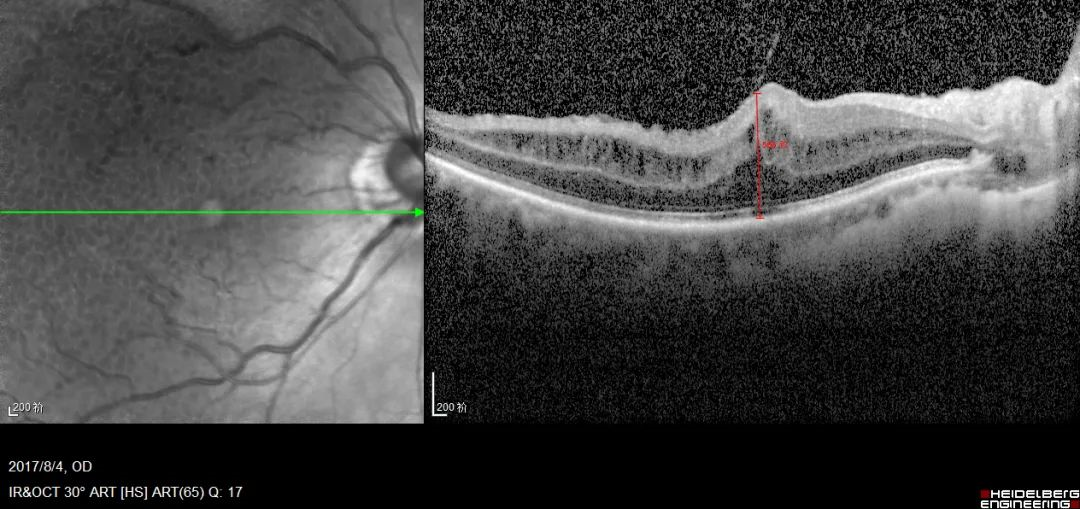

黄斑前膜的oct表现:黄斑前膜手术:采用微创玻切手术,仔细将黄斑区

术后黄斑部oct显示前膜已被完整剥除,见下图